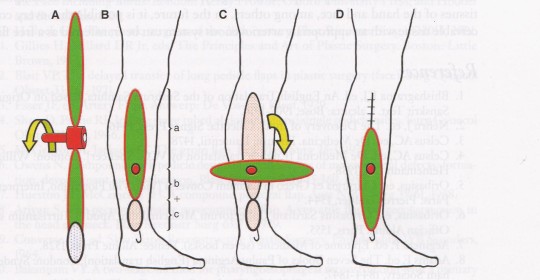

Лоскут, поднятый на осевом сосуде и отделенный от кожных краев становится островковым, и может быть перемещен на область дефекта различными способами. При перемещении путем аксилярной ротации лоскут становится похож на вращающийся пропеллер, что и обеспечило закрепление такого термина. Термин «propeller flap» или «лоскуты типа пропеллер» был введен в 1991 году в публикации Hyakusoku et al. [14], где описаны лоскуты этого типа на ножке из подкожных тканей со случайным выбором кровоснабжения и возможностью ротации на такой ножке до 90 град. Позднее, в 2006, Hallock [13] описал похожий лоскут, но уже на выделенной сосудистой ножке, что позволило увеличить дугу ротации до 180 град.

Таким образом, лоскуты типа пропеллер относятся к островковому типу лоскутов, которые после дессекции перемещаются в реципиентное ложе путем аксилярной ротации на питающей ножке таким образом, чтобы больший лепесток лоскута обеспечивал закрытие раневого дефекта (С) в реципиентной зоне, а меньший – закрытие донорской зоны (D) без существенного натяжения краев кожи (Рис. 3).

Рис. 3. Схема планирования и перемещения лоскута типа пропеллер для закрытия раневого дефекта; I – Позиция раневого дефекта (С) и лоскута (АВ) до проведения операции, звездочкой обозначена точка выхода перфорантной ветви артерии, которая формирует питающую ножку, определяет центр ротации (point pivot) и соотношение долей в лоскуте (большая доля А-звездочка и малая доля В-звездочка); Круговой стрелкой показана возможная степень ротации (90 град – 180 град.); II – Позиция лоскута (АВ) после его выделения и ротации на 180 град. в реципиентную зону, раневой дефект (С) полностью закрыт без натяжения тканей большой долей лоскута (А-звездочка), также проведено первичное ушивание донорской зоны (D) с использованием малой доли (В-звездочка).

В настоящее время наиболее широко используется техника Pedicle Perforator Propeller Flap (PPPF), когда сосуд питающей ножки не скелетизируют полностью, а оставляют 1-2 см фасциальной перемычки. Это обеспечивает, с одной стороны, не сложную и безопасную ротацию данного лоскута на 180 град. и более, с хорошей адаптацией и без натяжения кожи в реципиентном ложе, а с другой – перемычка защищает сосуд от перегиба или чрезмерного растяжения. Варианты формирования лоскутов по типу питающей ножки представлены на рис.4.

Рис. 4. Варианты формирования лоскутов по типу питающей ножки: А – островковый лоскут пропеллер на подкожной питающей ножке (subcutaneous pedicle propeller flap – SPPF), с аксилярной ротацией в реципиентную зону на 90 град.; Б – островковый лоскут пропеллер на питающей ножке, состоящей из выделенных изолированных перфорантных сосудов (perforator pedicle propeller flap – PPPF) с аксилярной ротацией в реципиентную зону на 180 град.